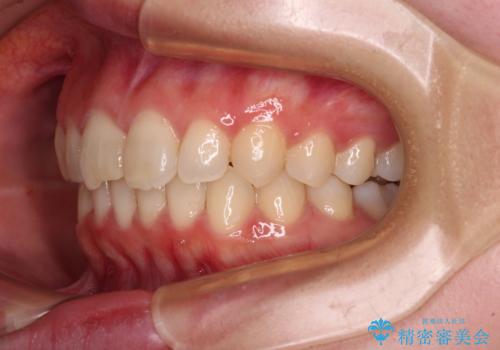

上下ともにデコボコの程度は著しいものではなく、インビザラインで十分に対応可能な歯列不正でした。

後戻りによりスペースができてしまうことを避ける目的で、IPR(歯と歯の間を削る)を極力用いない矯正治療を行うこととしました。